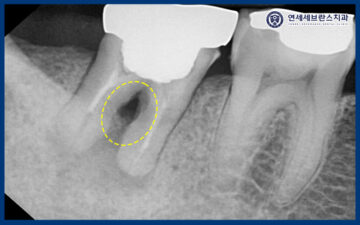

정밀한 상태 확인을 위해

파노라마 촬영을 진행하였습니다.

그 결과, 치조골 소실로 인해

크라운 내부 상태가 좋지 않을 가능성이

높게 확인되었습니다.

환자분께서는 치아를 살려

사용해보기를 원하셔서,

기존 크라운을 제거한 뒤

다시 평가하기로 하였습니다.

다만 뿌리가 이미 파절되어 있을 가능성도 있어,

보존 치료를 하더라도

사용 기간이 길지 않을 수 있음을

안내드렸습니다.